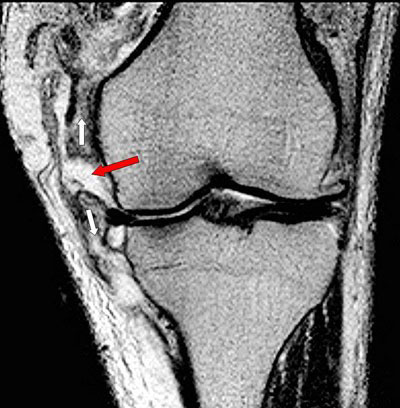

Scheur in de mediale band

Op de foto is bij de rode pijl de scheur in de mediale band op een MRI van de knie goed te zien. De witte pijlen geven de richting van de kracht aan die bij een valgusexorotatie trauma tot een scheur leidt van de mediale band die op de foto ook verdikt is.

In dit geval werd gezien de complexiteit van het trauma gekozen voor een operatieve behandeling door de mediale band te hechten alvorens in een later stadium de voorste kruisband operatief te herstellen. Ook in geval van een avulsiefractuur van de aanhechting aan het bovenbeen (op de röntgenfoto meestal goed zichtbaar) wordt, indien het fragment is verplaatst, een operatieve behandeling gedaan en het geavulneerde fragment gefixeerd met een schroef of kram. Uitgestelde behandelingen van niet goed genezen mediale bandletsels zijn minder succesvol.